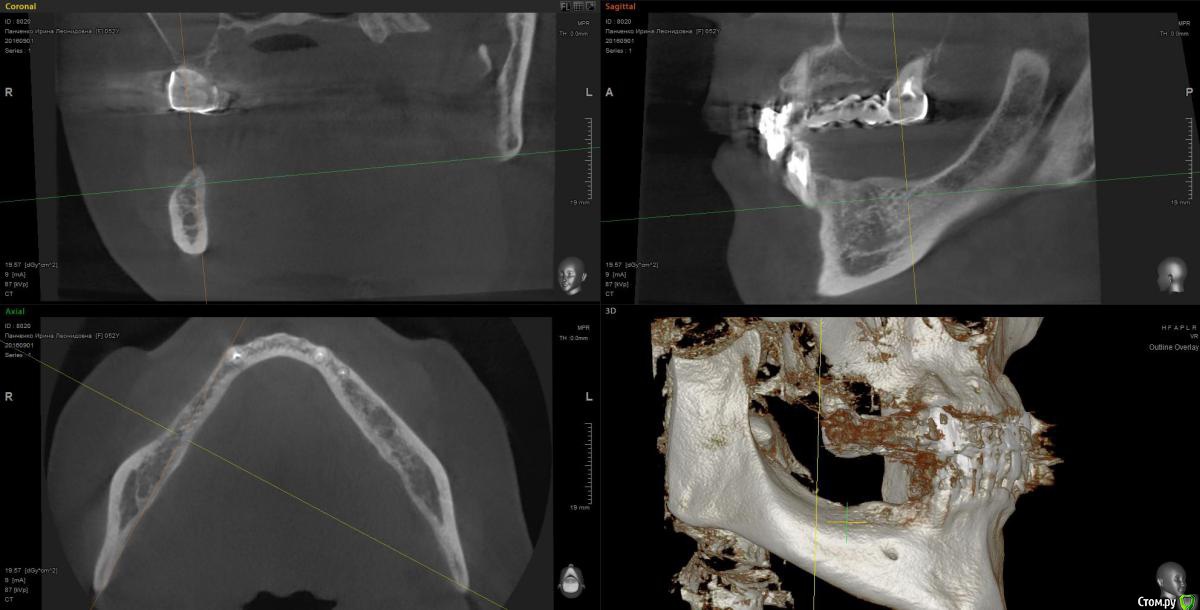

Kostoprav Опубликовано 13 марта, 2017 Поделиться Опубликовано 13 марта, 2017 рецепт сосиски: 70%биопласт by владмива +30%аутокость, мембрана hyprosorb кт до кт сразу после имплантации кт через пол года 3 Ссылка на комментарий